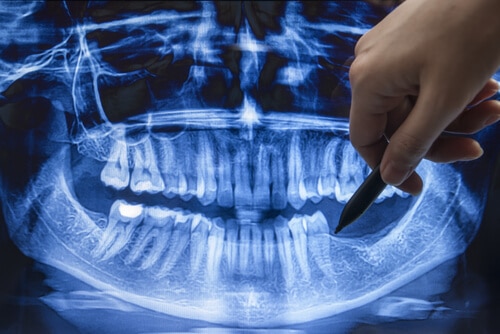

Digital dental x-rays provide higher-quality images than traditional dental x-rays. They produce very clear and detailed images that are more accurate than those from traditional film x-rays.

Images from digital dental x-rays are also easy to manipulate for better visualization. This allows dentists to enhance the clarity of the images further. Enhanced images from digital x-rays can better display problem areas.

Digital dental radiography also allows for more precise measurements. This helps dentists diagnose and treat conditions with greater accuracy. Digital images can then get stored for future reference.